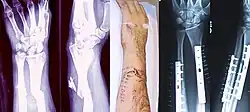

- Distal radius fracture

- Colles' fracture – a distal fracture of the radius with dorsal (posterior) displacement of the wrist and hand

- Smith's fracture – a distal fracture of the radius with volar (ventral) displacement of the wrist and hand

- Barton's fracture – an intra-articular fracture of the distal radius with dislocation of the radiocarpal joint

When the initial post-fracture oedema or swelling goes down, the fracture may be placed in a removable brace or orthosis. If being treated with surgery, surgical nails, screws, plates, and wires are used to hold the fractured bone together more directly. Alternatively, fractured bones may be treated by the Ilizarov method, which is a form of an external fixator.